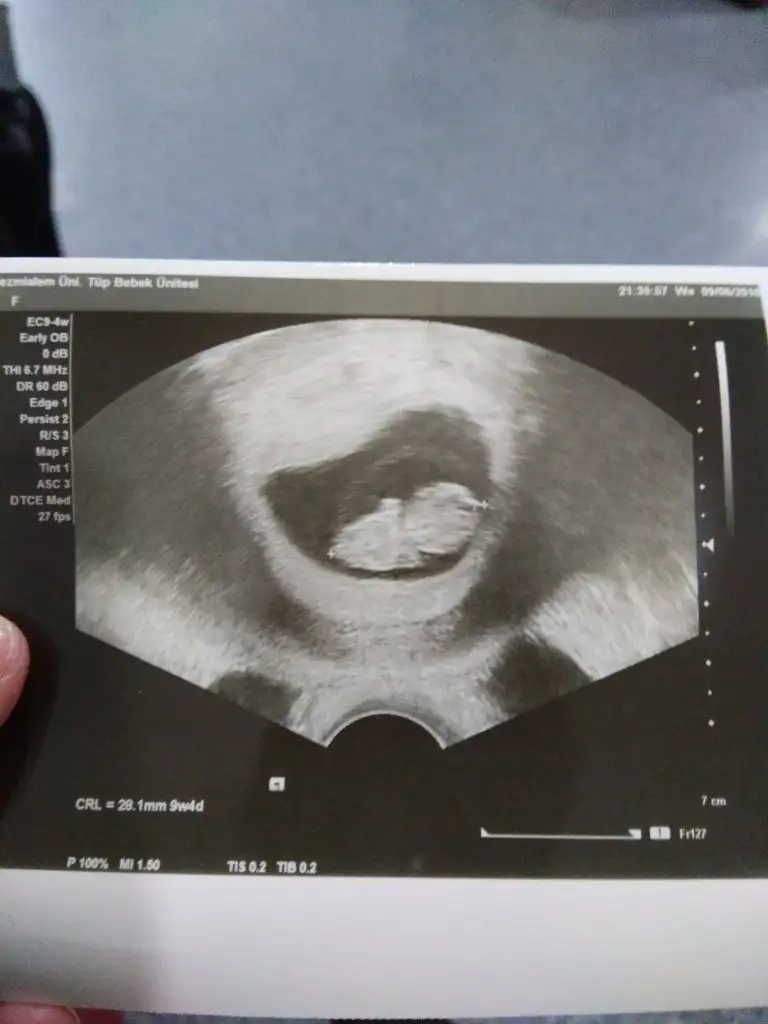

Burdayim kizlar merak etmeyin sadece sessizce okuyorum yazdiklarinizi nub teorisi varmis burda biri usg resimlerine gore tahminde bulunuyor 11 12 13 haftaki fotolarla ben 9 haftalik usg attim rica ettim kiza benziyor dedi bakalim dogru cikacakmi